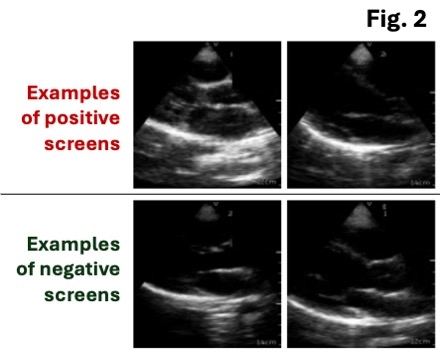

Results: Our model (Fig. 2) achieved a study-level AUROC (area under the receiver operating characteristic curve) of 0.88 across the held-out/external testing sets for identifying stage ≥B RHD from cardiac POCUS (Fig. 3A). On a video-level the model learned a continuous spectrum of phenotypes on PLAX acquisitions spanning stage ≥B (“definite”) and stage A (“borderline”) cases, ranging from a median video-level AI probability of 0.13 [0.01-0.73] for stage ≥B to 0.00 [0.00-0.01] for non-RHD POCUS (Fig. 3B). At the threshold that maximized Youden’s J in the held-out Brazil set, our algorithm’s performance in the set from Uganda showed 97% recall (sensitivity), a positive predictive value (precision) of 46%, and a negative predictive value of 95%.